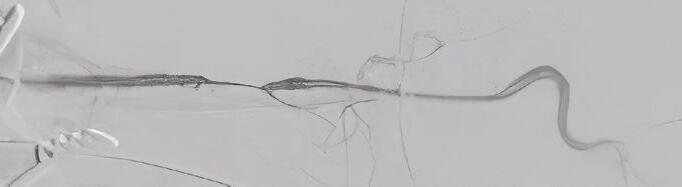

TCAR is a less invasive, clinically proven, approved treatment option for carotid artery disease. The procedure begins with a small incision just

above the clavicle. A temporary sheath is placed directly into the carotid artery in an area away from the disease. The sheath connects to a filter and flow reversal system outside of the body and then to another small sheath that is placed directly into the femoral vein. The difference in pressure causes the reversal of blood flow away from the brain, decreasing the risk of a stroke. A stent is then inserted through the sheath to open the stenotic and diseased carotid artery. Because of the blood flow reversal, any debris that might break loose during stent placement won’t travel up to the brain, rather it travels downward and gets trapped in the filter, and the filtered blood returns into the vein.

TCAR procedure showing severe carotid stenosis on initial angiogram (top) followed by stent deployment and final angiogram with resolution of the stenosis (bottom).

Proper selection and identification of patients who are candidates for TCAR is critical. TCAR is now available for patients of all risk levels, including those with symptomatic and severe asymptomatic carotid stenosis as well as high anatomical or medical risk for open surgery.

Since 2022, Cleveland Clinic Weston Hospital has performed TCAR routinely using a minimally invasive approach. Our center performs the highest volume of TCARs in South Florida. Outcomes have been excellent, with 100% technical success rate and no reported strokes for our patients. Our expertise in open vascular surgery and CEA combined with newer, advanced endovascular techniques such as TCAR, has translated into the best possible patient outcomes.